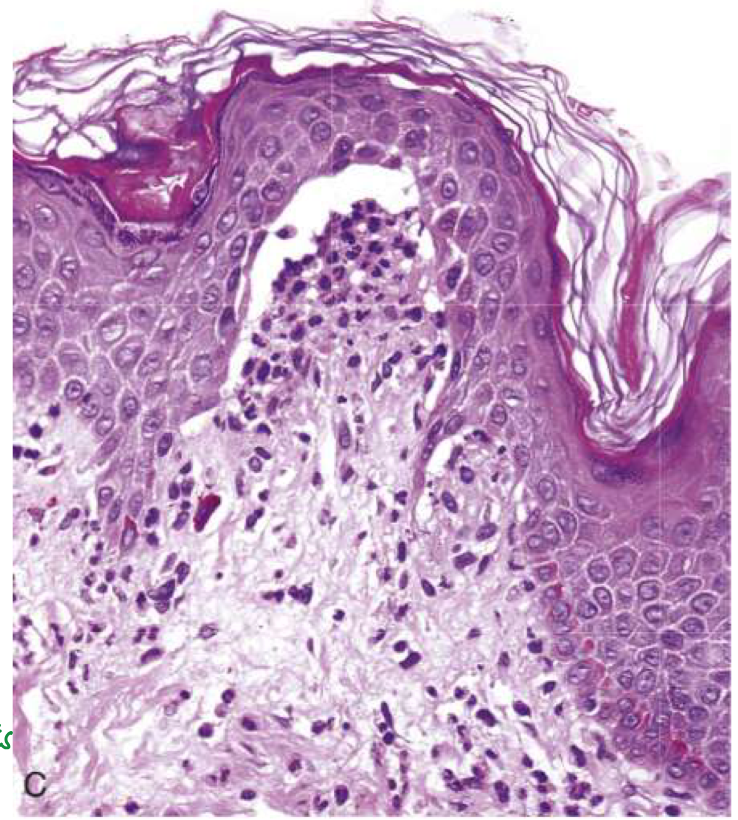

Suprabasal acantholytic blister histology

row of tombstones, intact basal cells at base of blister

pemphigus vulgaris

Portion of epidermis (including stratum corneum) forms the roof of bullae